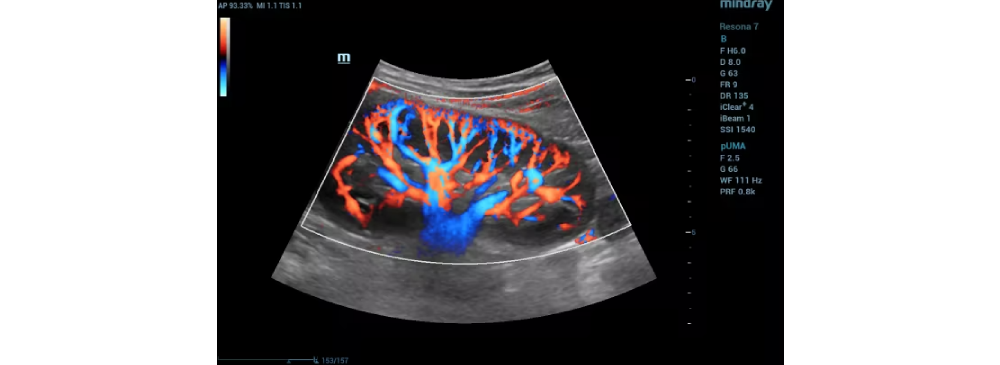

A Renal Doppler Test is a highly specialized ultrasound scan that evaluates the blood flow to and from your kidneys. At our Insight Diagnostics and Labs Pallavaram, in Pallavaram, we offer this non-invasive test using advanced Doppler sonography to help detect and monitor kidney conditions, hypertension, and renal artery blockages with precision. This test plays a critical role in understanding the vascular health of your kidneys and helps doctors plan the right course of treatment for long-term kidney care.

The Renal Doppler Test is a type of ultrasound scan that uses sound waves to examine how blood flows in the arteries and veins of your kidneys. Unlike regular ultrasound, this Doppler variation can assess both the speed and direction of blood flow, helping doctors detect abnormalities like blockages or narrowing in renal arteries. It’s completely safe, radiation-free, and suitable for people of all age groups.

• Detailed color Doppler images for accuracy